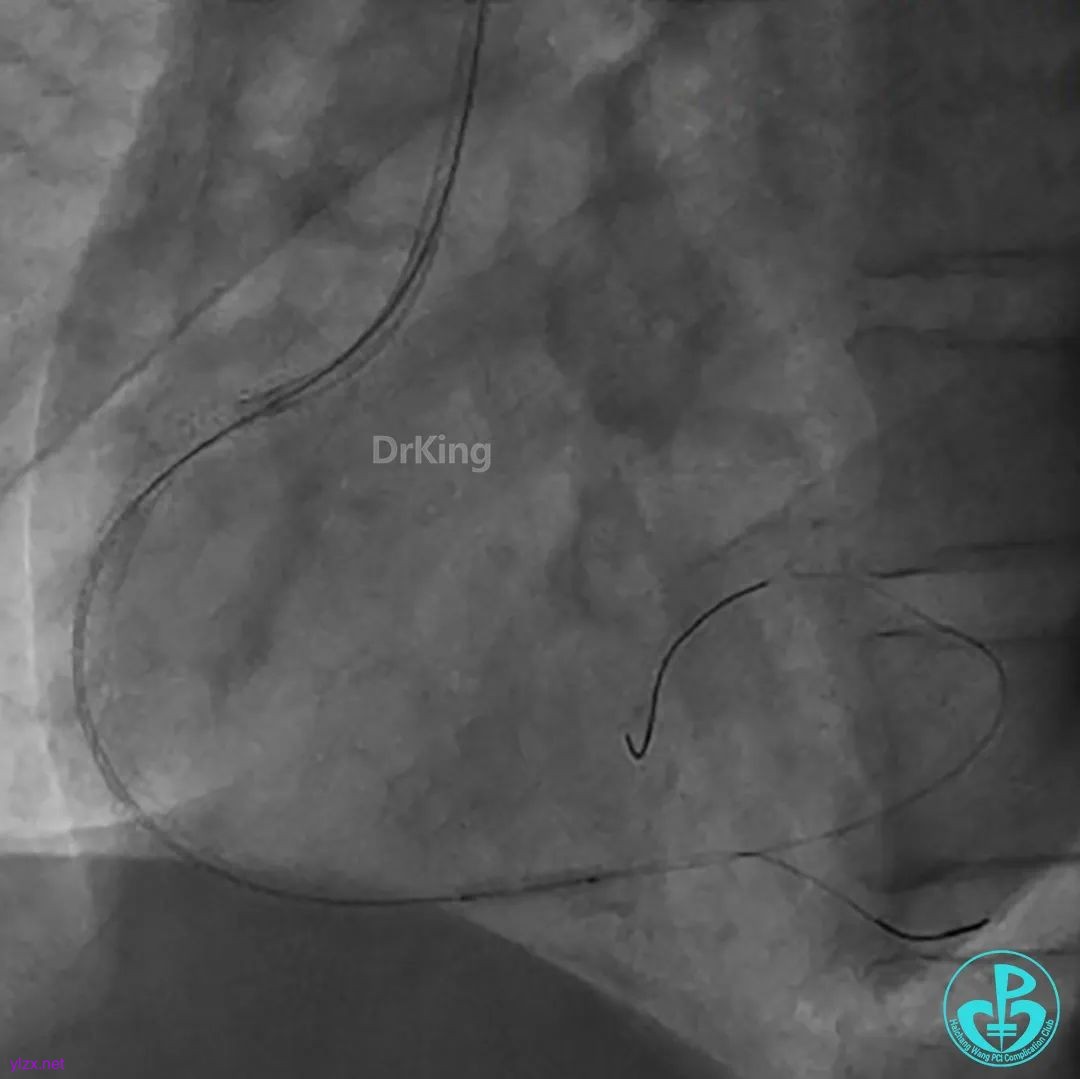

导管、导丝飞走。

导管、导丝重新到位,血栓抽吸后,经抽吸导管注射替罗非班,血栓负荷减少,残余狭窄重。

球囊再次扩张远端后,替罗非班注射,示远端狭窄改善,近端出现什么情况?血栓?夹层?

直接指引导管抽吸,未见血栓。

冒烟显示近端仍然有异物,远端造影剂滞留。

高度怀疑近端夹层。